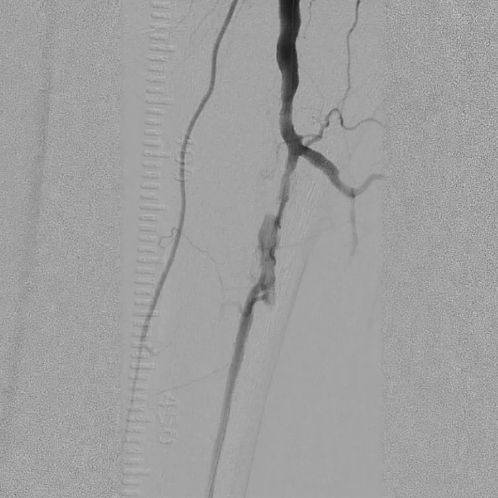

造影评估与通路建立

造影显示左侧胫腓干动脉闭塞,胫后动脉通过侧支循环显影,左侧腓动脉及胫前动脉全程闭塞。